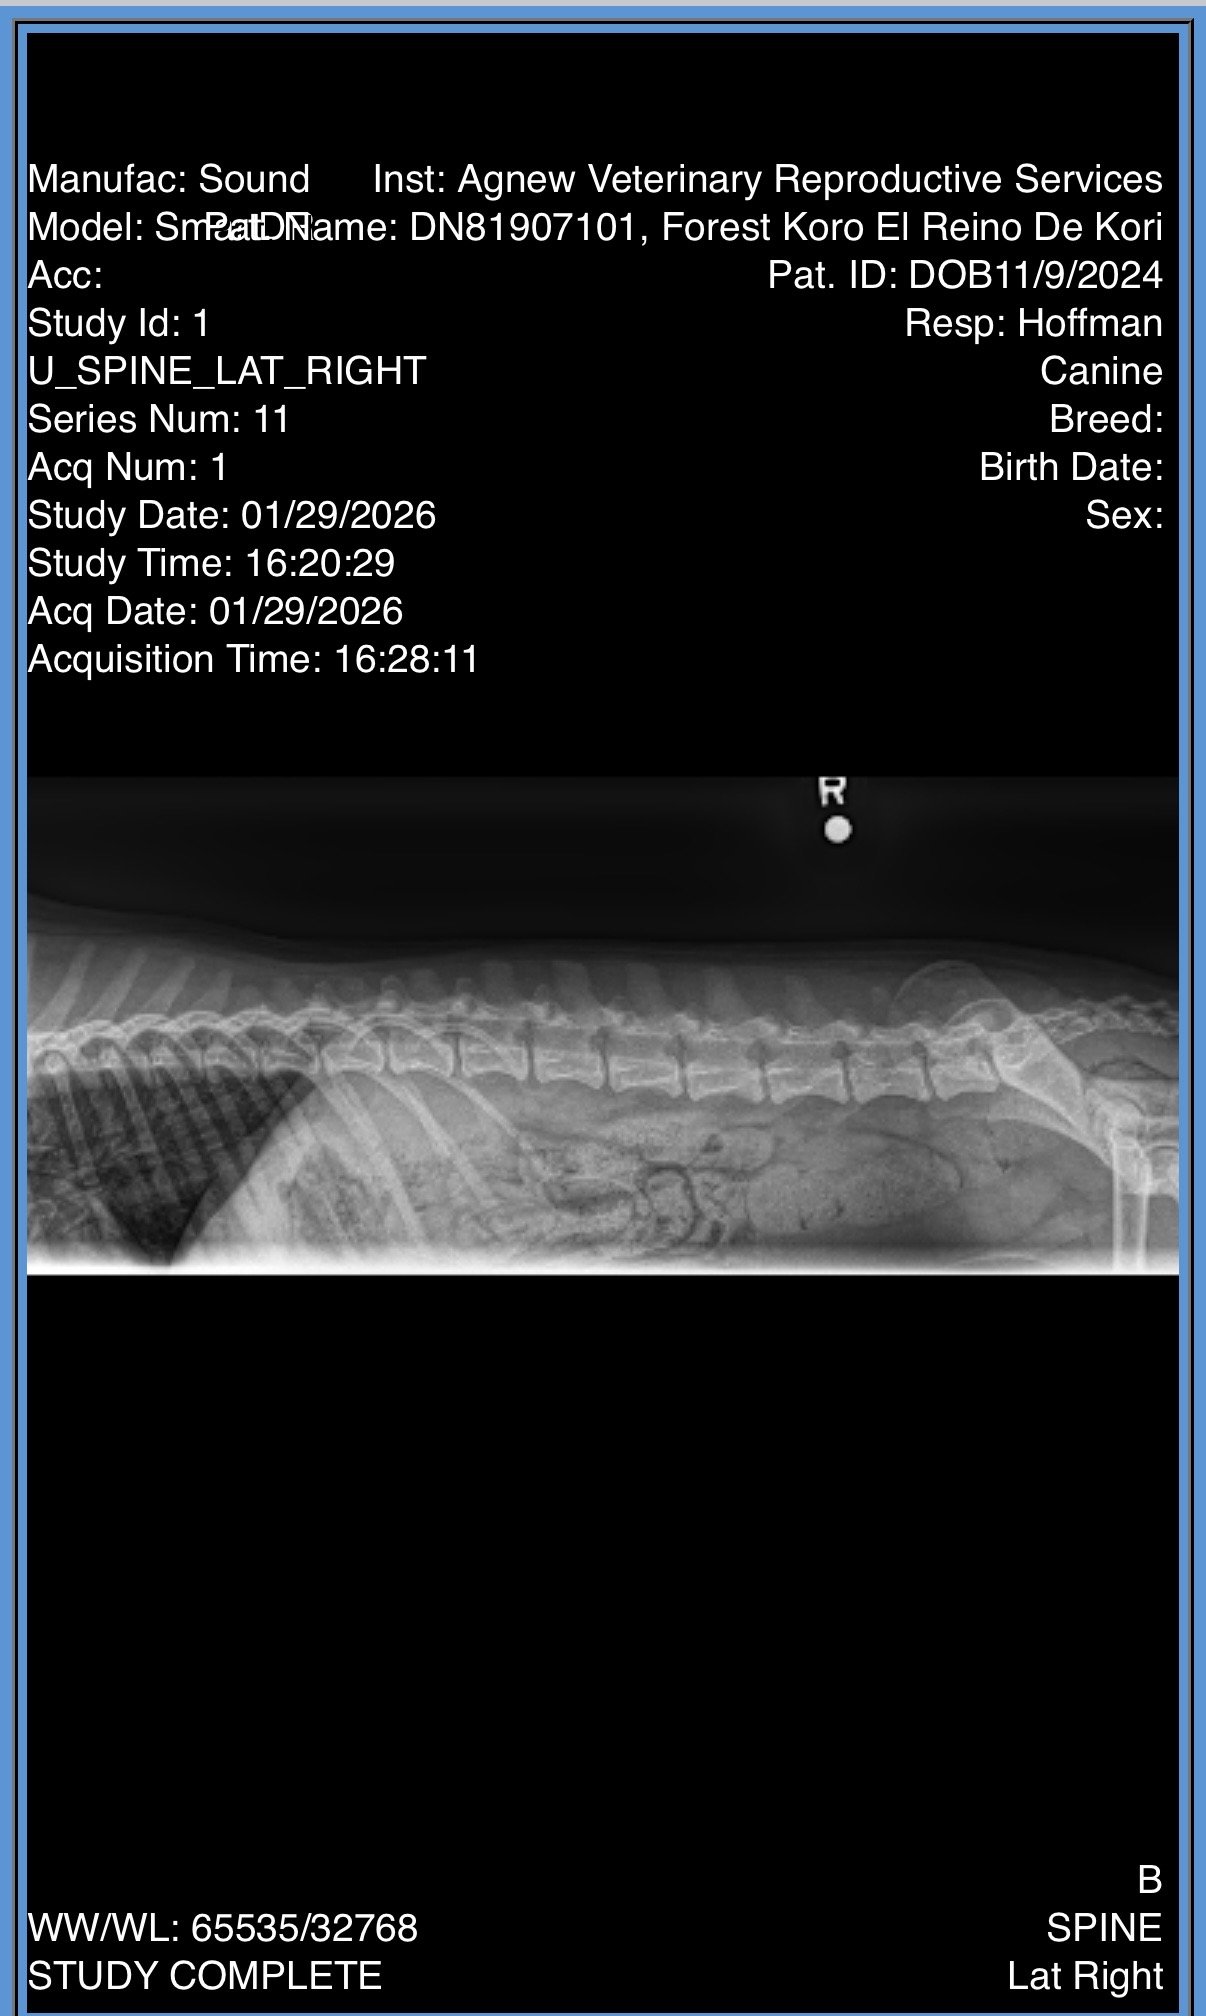

CH Forest Koro El Reino De Kori “Kpot”

Kpot was imported from Poland in 2025 from a kennel that focuses on conformation and agility. He is a sweet guy who earned his AKC championship at 9 months. Kpot was Winners Dog and BOS in puppy sweeps at the Mudi National 2025 and he is starting his agility journey and chipping away at his GCH!